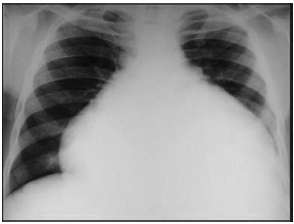

Identifique o achado de exame físico que pode estar associado à condição identificada na radiografia abaixo.

Provas